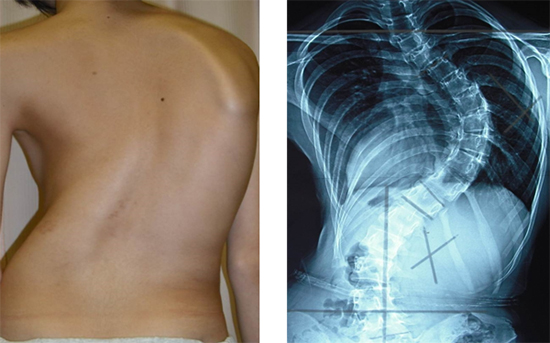

側彎(そくわん)とは、背骨が横に曲がった状態をいいます(図1)。ヒトの背骨は完全に真っ直ぐではありませんが、曲がりの角度が10度以上になると病的(側彎症)と考えられています。曲がりの角度が20度を超えると、装具の着用など何らかの治療をする必要が生じ、40度を超えると、多くの場合手術治療が必要となります。さらに重度になった場合は、肺機能が低下し、腰痛や背部痛の発症が増加するとされています。進行すると治療が困難になるので、早期発見と進行予測が大切です。

図1 側彎症

左:側彎症患者の外観。右:脊椎X線画像(背面図)。背骨が大きく弯曲している。